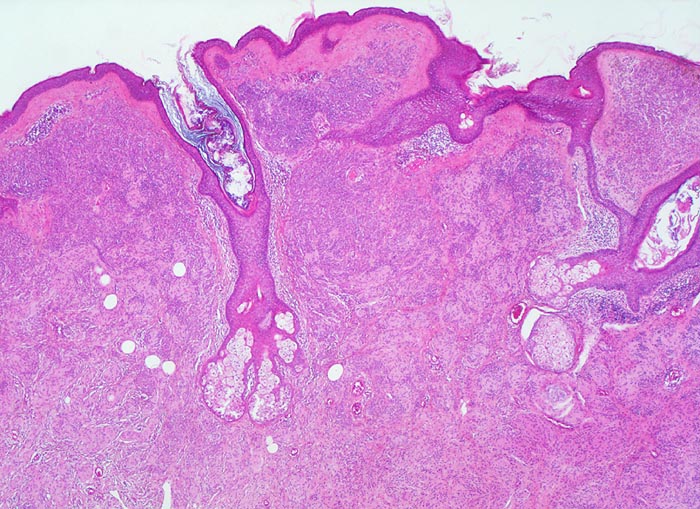

• Symmetrischer leicht exophytischer Tumor.

• Die Tumorzellen bilden Nester in der Epidermis und in der Dermis (=dermoepidermaler bzw. compound Naevus).

• Oberflächliche Tumorzellen enthalten teilweise körniges braunes Melaninpigment.

• Angrenzend an die pigmentierten Zellnester sind Melanophagen erkennbar, deren Zytplasma mit Melaningranula angefüllt sind.

• Die oberflächlichen Naevuszellen zeigen reichlich helles, teils pigmentiertes Zytoplasma und helle ovale Kerne mit kleinen, deutlich erkennbaren Nukleolen. Zur Tiefe hin werden die Naevuszellen kleiner, haben weniger Zytoplasma und dunkle kleine Kerne ohne gut erkennbaren Nucleolus. Die Zellnester werden zur Tiefe hin ebenfalls kleiner (=Ausreifung).

• Keine Mitosen, keine Zellatypien.

Erworbene Naevi können ein lentiginöses oder ein kongenitales Wachstumsmuster aufweisen (Ausbreitung der Naevuszellen in der tieferen Dermis entlang von Adnexstrukturen). Letzteres bedeutet nicht, dass der Naevus bei Geburt schon bestand. Am Anfang der Entwicklung erworbener Naevi steht die Lentigo simplex (> 5299), welche durch Vermehrung einzeln liegender Melanozyten im Bereich der basalen Epidermis zustande kommt und makroskopisch als scharf begrenzte braune Makula imponiert. Daraus entwickeln sich junktionale Naevi mit Nestern von jeweils drei oder mehr Naevuszellen in der basalen Epidermis (> 5362). Bei Compound Naevi (= dermoepidermaler Naevuszellnaevus) finden sich zusätzlich zu den epidermalen auch intradermal gelegene Naevuszellen oder Nester von Naevuszellen (> 565). Compound Naevi zeigen ein sehr variables makroskopisches Bild von gering erhabenen bis zu polypoiden, gestielten oder verrukösen Läsionen. Die Farbe variiert von braun über grau bis zu hautfarben. Diese Naevi bleiben über Jahre weitgehend unverändert und entwickeln sich schliesslich weiter zu rein dermalen (=corialen) Naevi mit ausschliesslich intradermal gelegenen, oftmals unpigmenierten Naevuszellen, um schliesslich vollständig zu verschwinden.